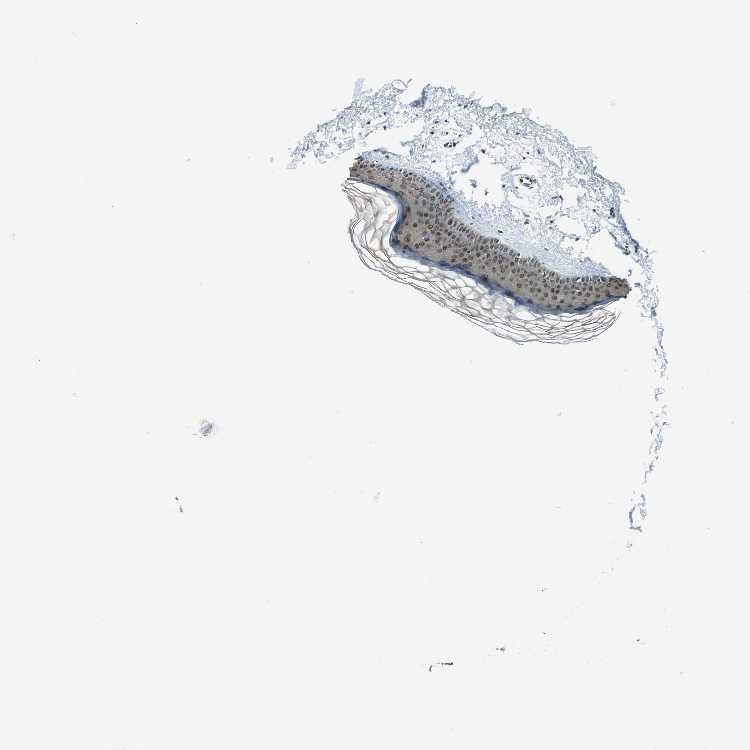

SKIN 1 - Antibody stainingi

Antibody staining in the annotated cell types in the current human tissue is reported as not detected, low, medium, or high, based on conventional immunohistochemistry profiling in selected tissues. This score is based on the combination of the staining intensity and fraction of stained cells.

Each image is clickable and will lead to virtual microscopy that enables deeper exploration of all samples and also displays staining intensity scores, fraction scores and subcellular localization as well as patient and tissue information for each sample.

Antibody HPA006628

Langerhans Medium

Fibroblasts Medium

Keratinocytes Medium

Melanocytes Not detected

SKIN 2 - Antibody stainingi

Epidermal cells High